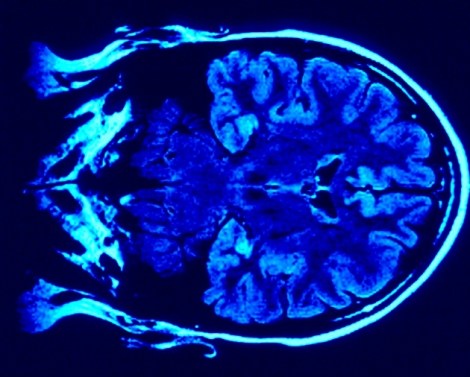

La neuroplasticidad es la capacidad que tienen nuestros cerebros de formar y reformar redes neuronales a partir de nuestras experiencias, es decir, la habilidad de moldearse con el aprendizaje.

Cuando estamos aprendiendo algo nuevo, se forman redes en nuestro cerebro a partir de neuronas que se comunican entre ellas a través de estructuras que permiten el pase de señales de una neurona a otra, conocidas como sinapsis. Una mejor comunicación entre neuronas está dada por un paso más eficiente de estas señales.

Cada vez que aprendemos o practicamos algo, estas conexiones se forman, o se refuerza la comunicación de conexiones existentes. Antiguamente se creía que las conexiones que se formaban durante nuestro crecimiento quedaban estáticas, pero hoy se sabe que la fuerza de estas conexiones puede variar de acuerdo con el uso o desuso de las mismas. Esta extraordinaria capacidad se conoce como plasticidad sináptica y es un concepto clave en el estudio del aprendizaje y la memoria.